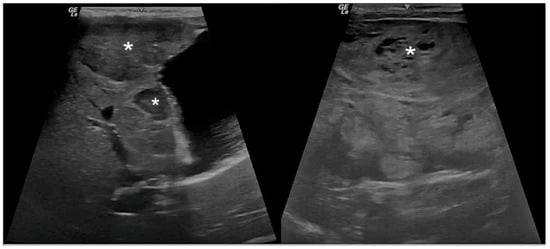

3.2. Ultrasound Examination

| Liver parenchyma homogeneity | 0.011 | ||

| Homogeneous (n (%)) | 20 (62.5) | 3 (27.27) | |

| Heterogeneous (n (%)) | 12 (37.5) | 8 (72.72) | |

| Liver parenchyma echogenicity | 0.053 | ||

| Hyperechoic (n (%)) | 30 (93.75) | 8 (72.72) | |

| Hypoechoic (n (%)) | 1 (3.12) | 0 (0) | |

| Heteroechoic (n (%)) | 1 (3.12) | 3 (27.27) | |

| Hepatobiliary ultrasound score | <0.001 | ||

| Mild (score 0–2) (n (%)) | 0 (0) | 0 (0) | |

| Moderate (score 3–5) (n (%)) | 30 (93.75) | 0 (0) | |

| Severe (score 6–12) (n (%)) | 2 (6.25) | 11 (100) |